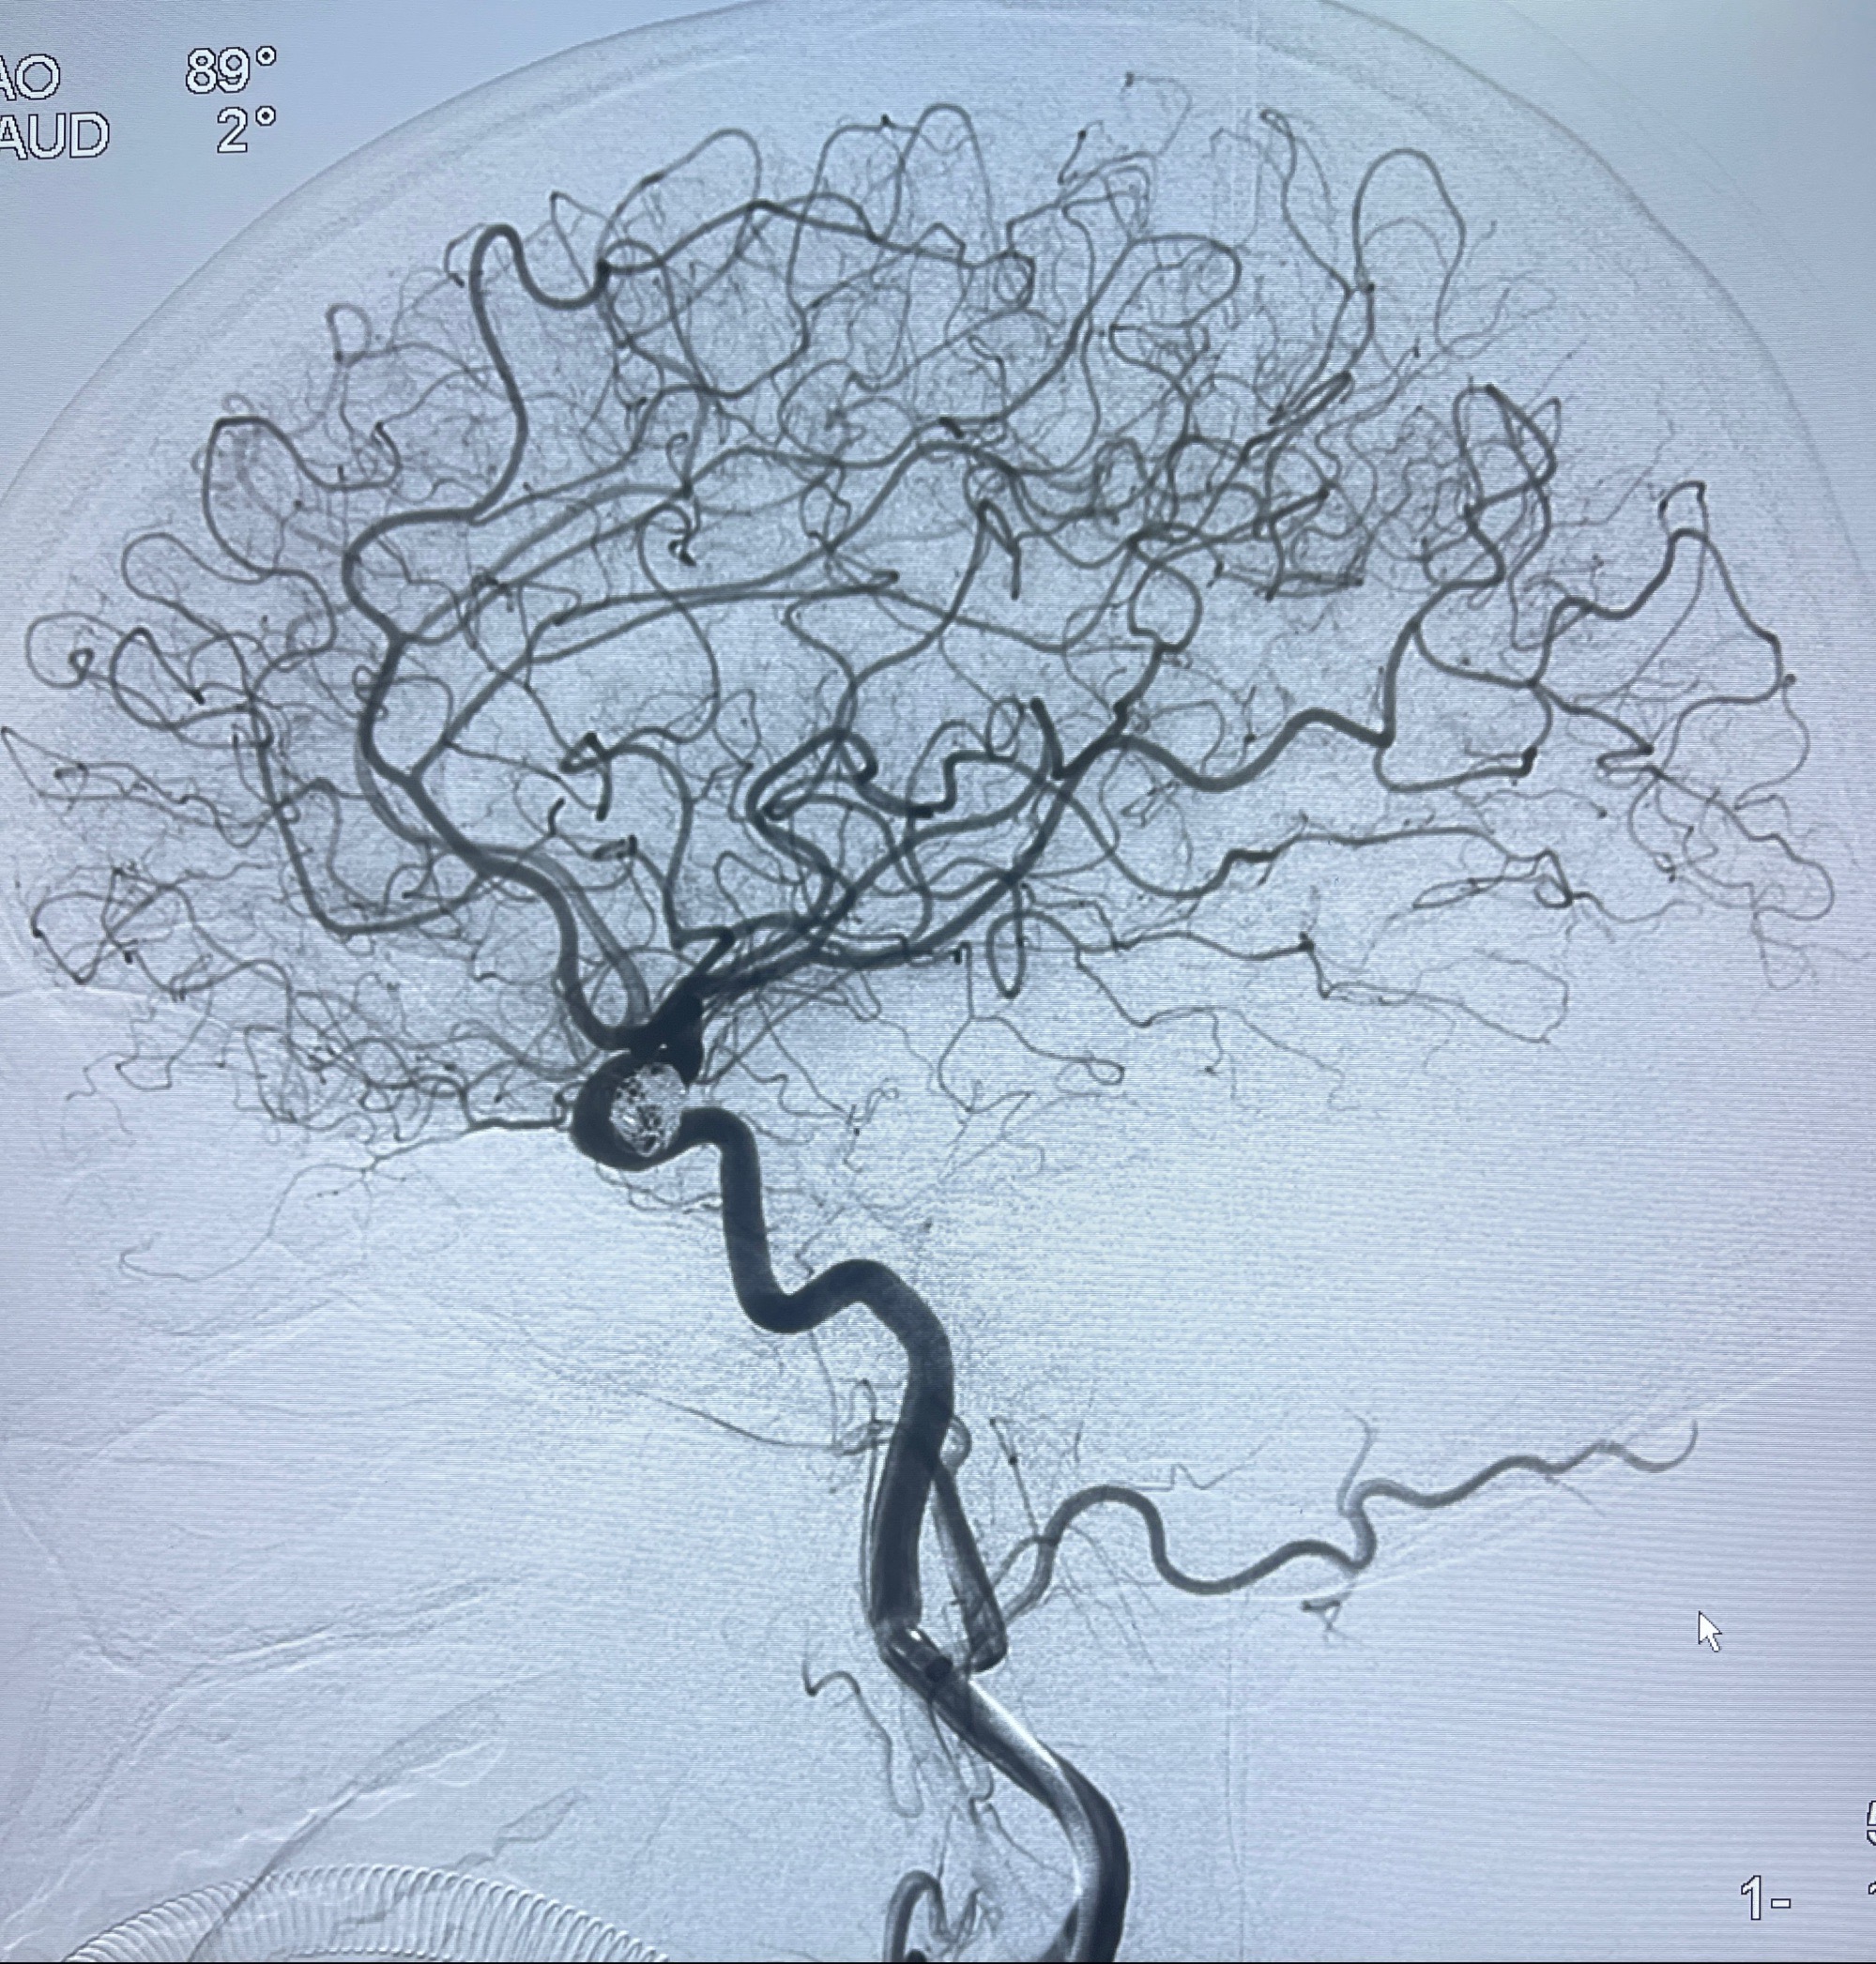

术后3D显示支架贴壁佳

麻醉苏醒佳,遵嘱活动!视力视野正常。